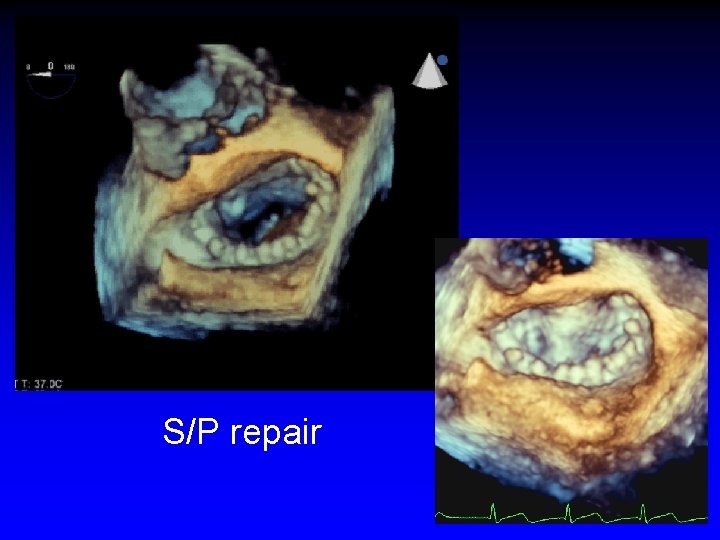

S/P repair